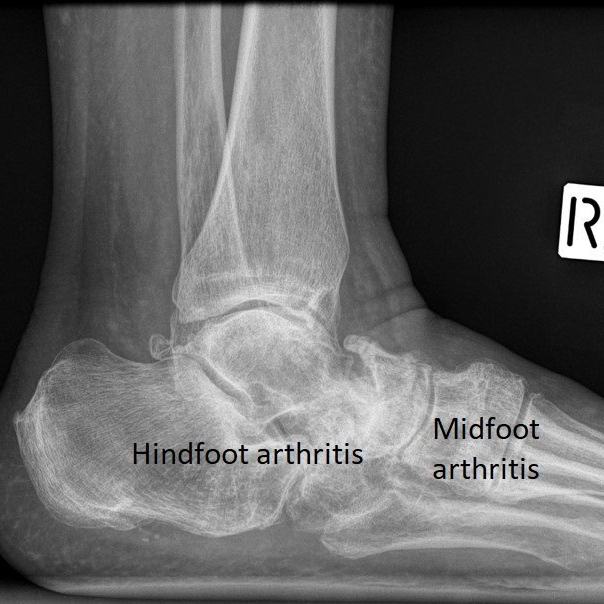

- midfoot joints (tarsometatarsal and naviculocuneiform)

- hindfoot joints (subtalar, talonavicular and calcaneocuboid).

Midfoot and hindfoot arthritis

- there are two surgical options:

- "clean-out" - removal of large spurs and inflammation

- fusion - permanently stiffening arthritic joints together with plates, screws and staples.

- There are no joint replacements available for the midfoot and hindfoot joints.